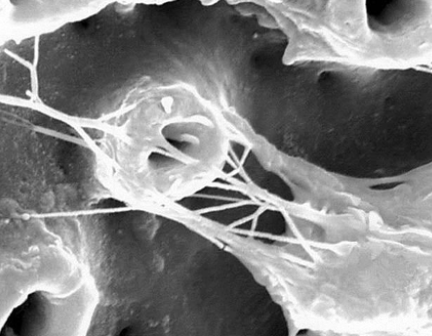

This is an example of failing implant-bone healing

Fibrous granulation tissue

What is the bone tissue response?

Fibrous tissue formation may occur ):

Non-vital bone may remain without revascularization ):

Bone healing will ensue :)